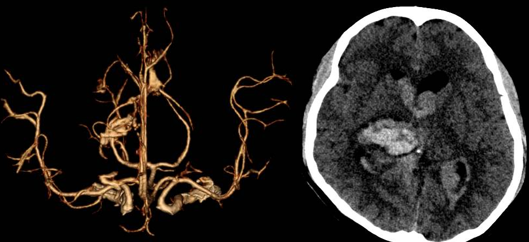

Đây là một nguyên nhân hàng đầu gây nên đột quỵ ở người trẻ tuổi. Sự phát triển bất thường của mạch máu não sẽ gây nên những túi phình dẫn đến đột quỵ xuất huyết não hoặc mạch máu có thể bị bóc tách gây hẹp - hay gọi là đột quỵ nhồi máu não. Dị dạng mạch máu não có thể phát hiện sớm qua phương pháp chụp cắt lớp vi tính tương phản mạch máu não, hoặc chụp cộng hưởng từ mạch máu não.

Xuất huyết não não - não thất nặng do vỡ dị dạng mạch máu não